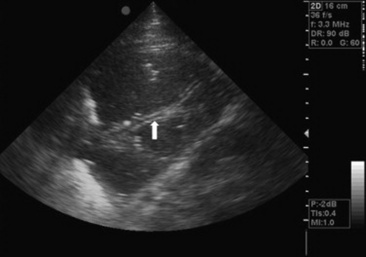

image

Fig. 31-3 Thoracocentesis and therapeutic drainage in the horse. Pleural effusion can be large and bilateral. Samples should be obtained for culture and cytologic examination at the time the chest is drained.

Courtesy Dr. Corinne Sweeney, University of Pennsylvania, New Bolton Center, Kennett Square, Penn.